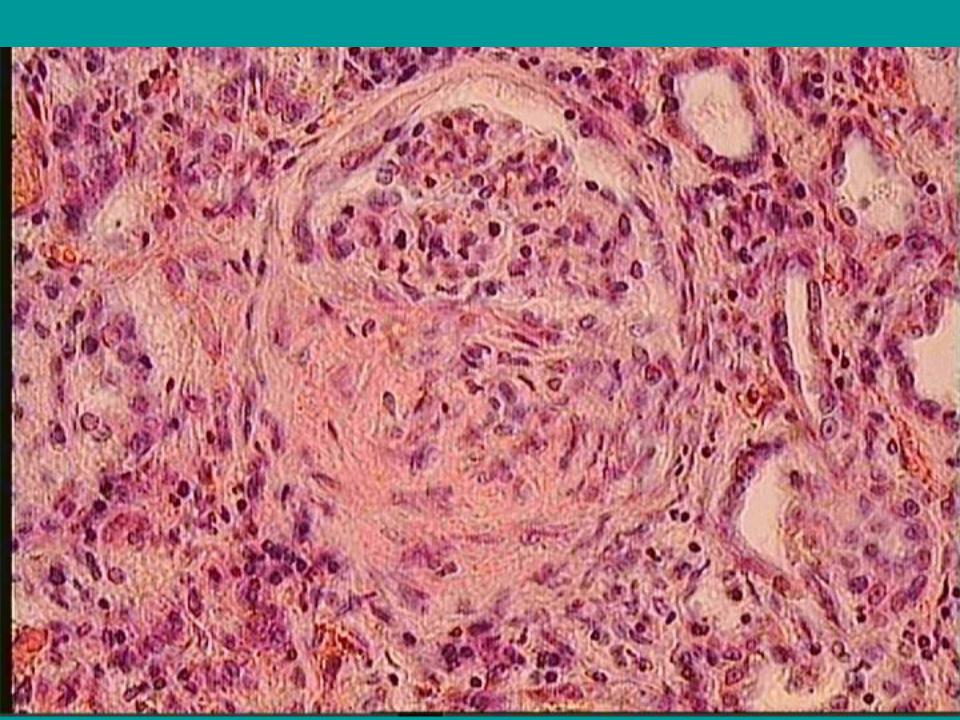

Симптомы подострого гломерулонефрита: фото и описание

Раздел: Визуальный дайджест